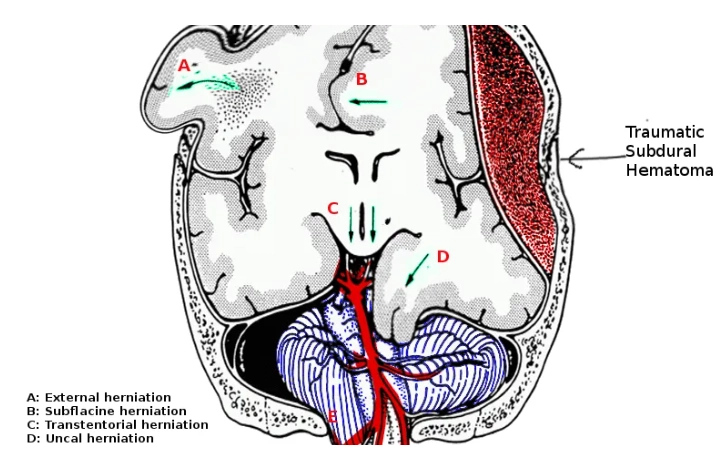

Thoát vị não (Brain herniation)

Thoát vị dưới liềm (Subfalcine Herniation - SFH)

Thoát vị móc hải mã (Uncal Herniation)- Thoát vị xuyên lều xuống dưới một bên (Unilateral Descending Transtentorial Herniation)

Thoát vị trung tâm (Central Herniation)-Thoát vị xuyên lều xuống dưới hai bên (Bilateral Descending Transtentorial Herniation)